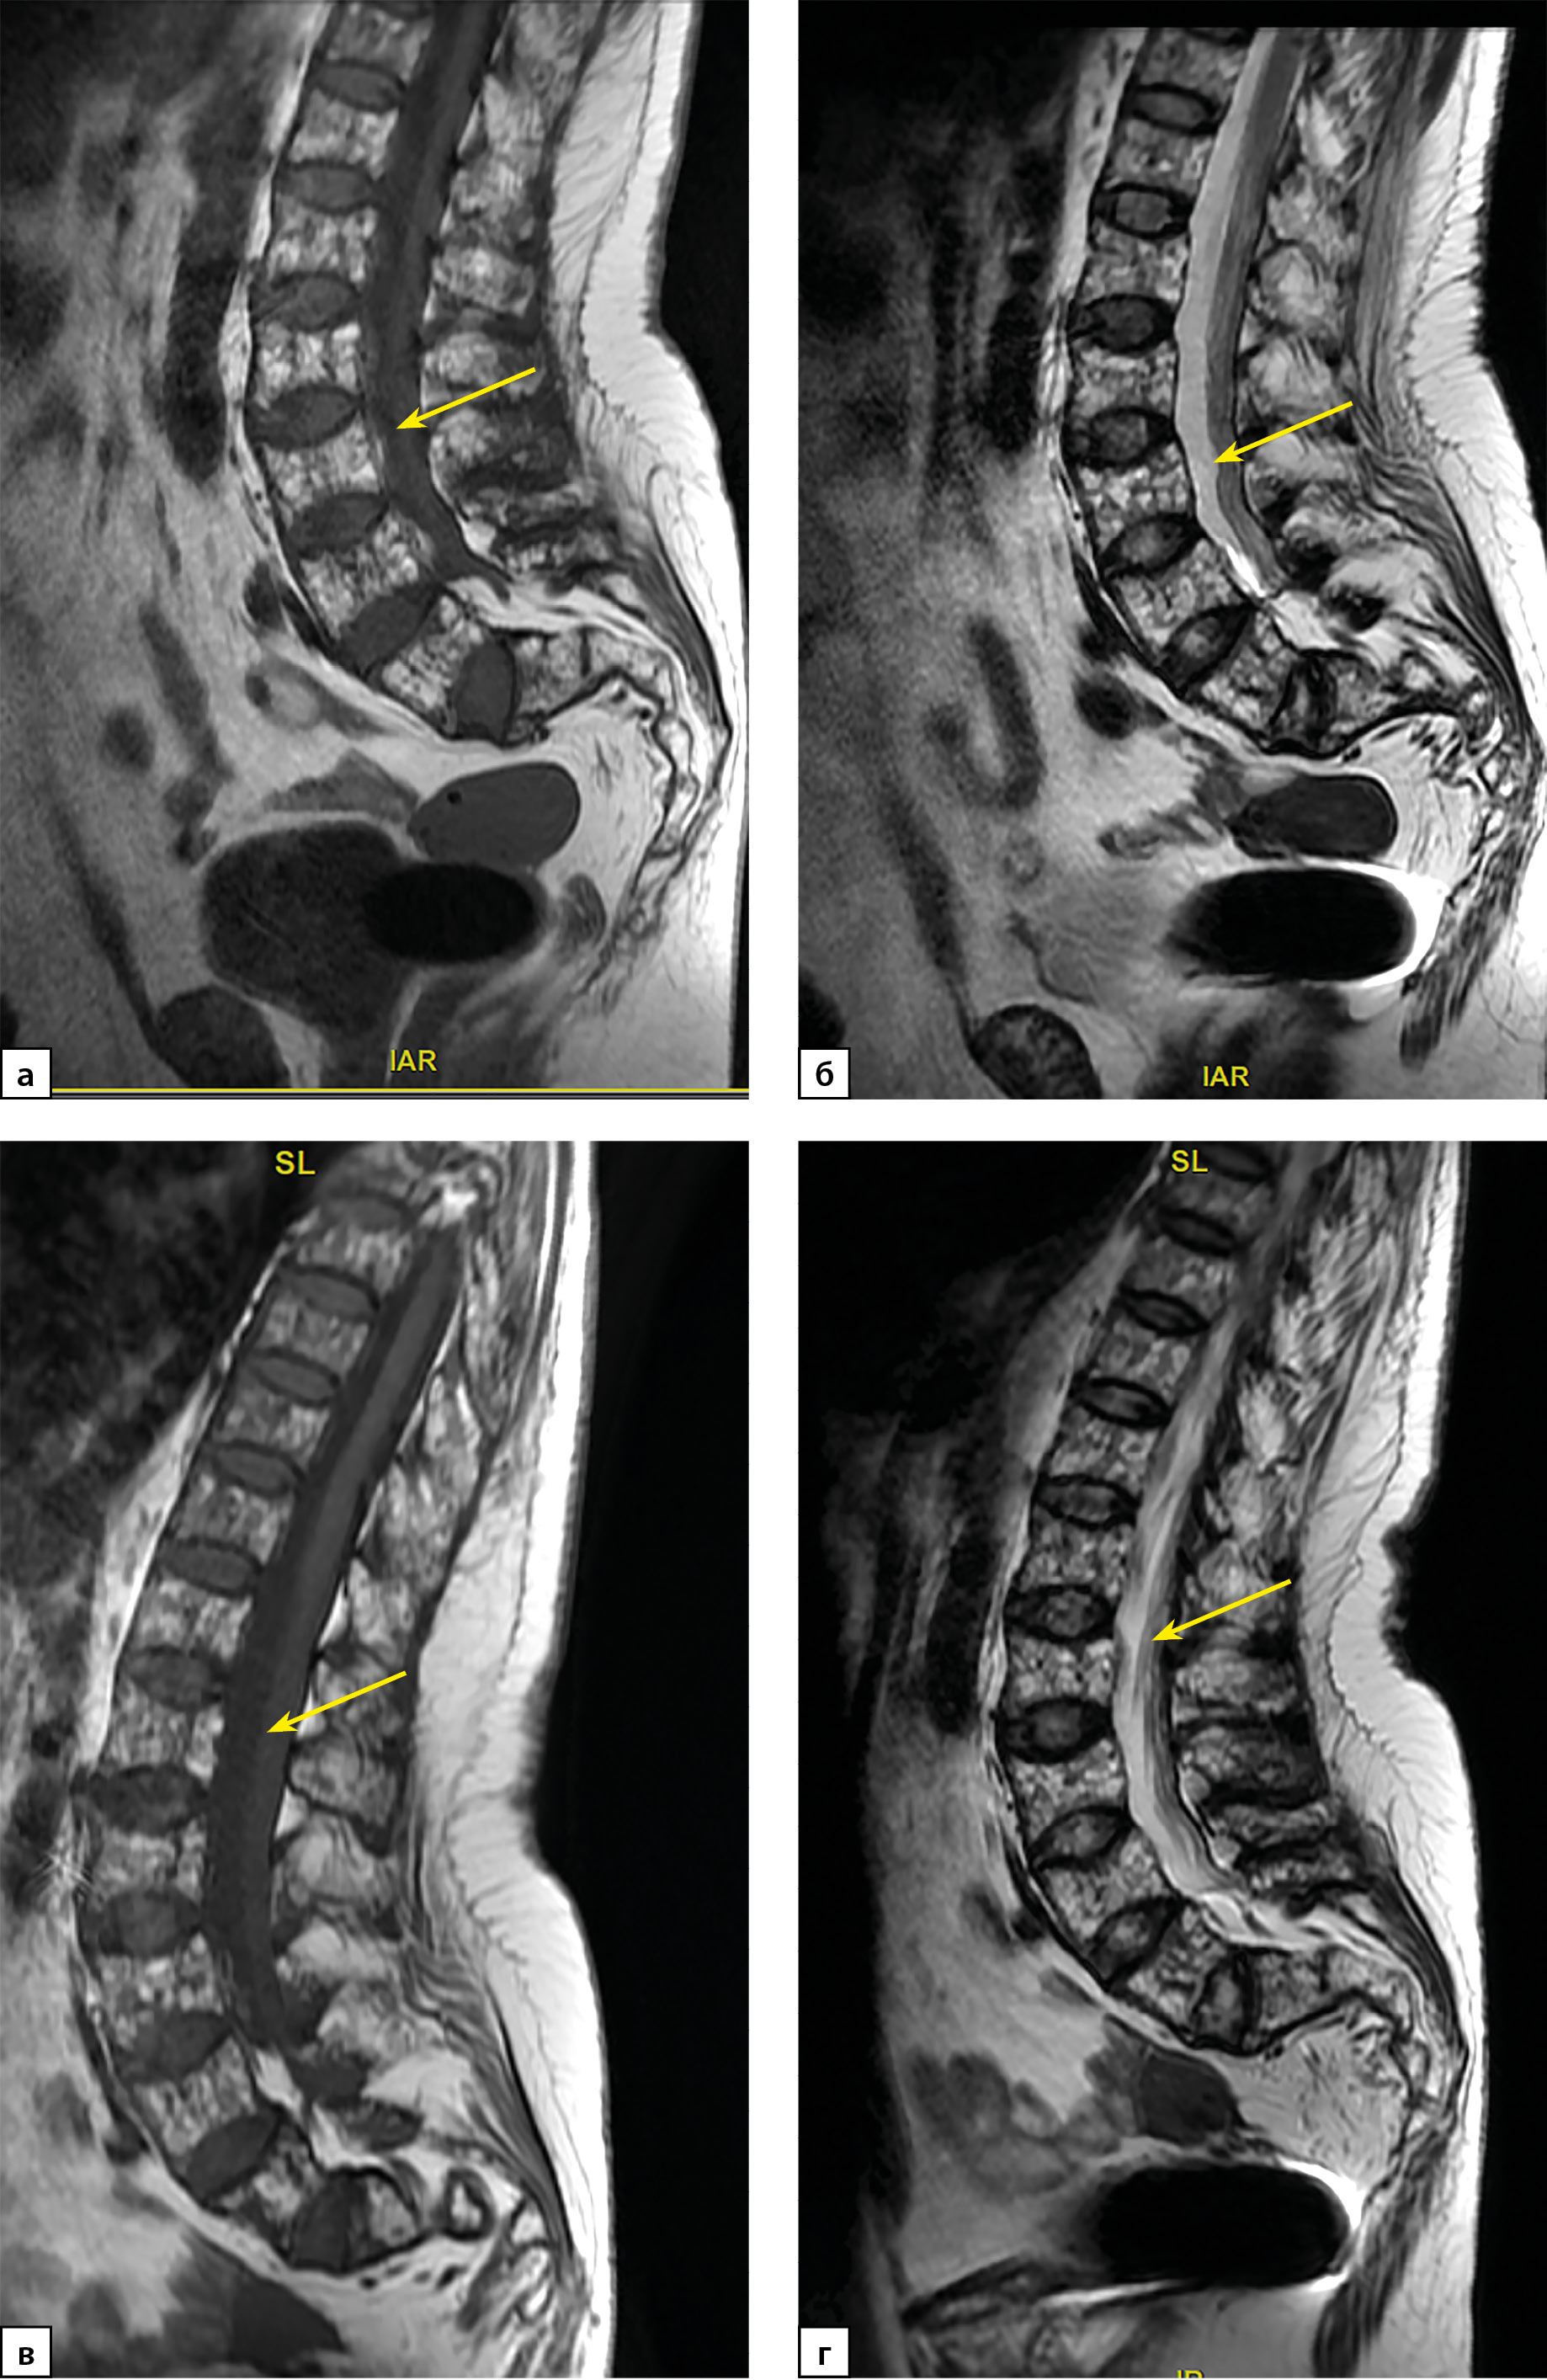

2. Рисунок 2. Пациентка П. МРТ-исследование поясничного отдела позвоночника в сагиттальной проекции: а) МРТ от 2021 г. Т1 ВИ, б) МРТ от 2021 г. Т2 ВИ; в) МРТ от 2022 г. Т1 ВИ; г) МРТ от 2022 г. Т2 ВИ. Определяется выраженное (более 40%, 3 ст.) снижение высоты тел позвонков с формированием двояковогнутой их деформации («рыбьи позвонки»). МРТ-картина без динамики. | |